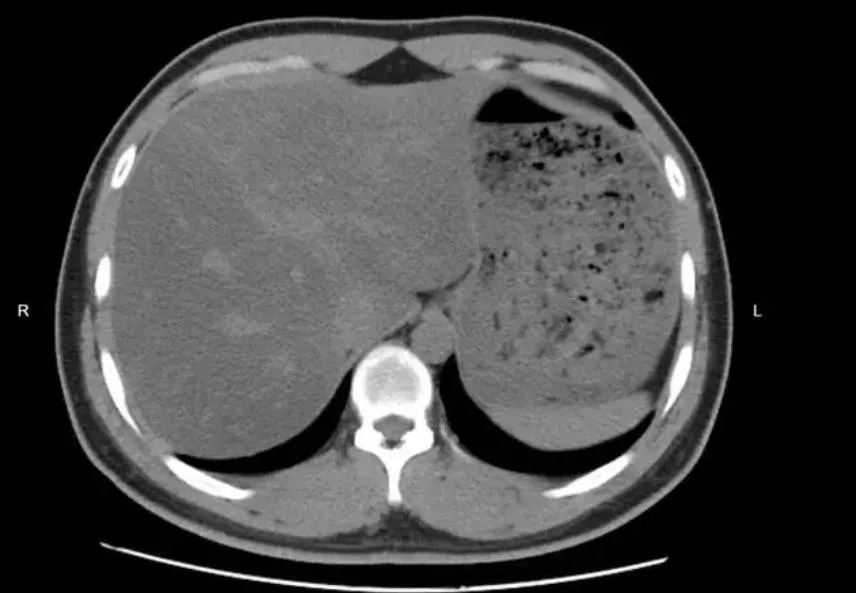

複檢發現吃素半年脂肪肝竟成中重度。(圖/翻攝大象新聞)